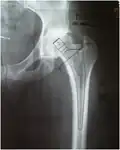

La planification opératoire est un élément commun à toutes les techniques : Le chirurgien détermine avant l'intervention la taille de la tige et du cotyle. Il dispose pour cela :

- soit de radiographies étalonnées précisément et de calques à la même échelle ;

- soit d'un logiciel qui permet cette programmation sur ordinateur.

Planification par calque pour pose de PTH.

Planification par ordinateur pour pose de PTH.